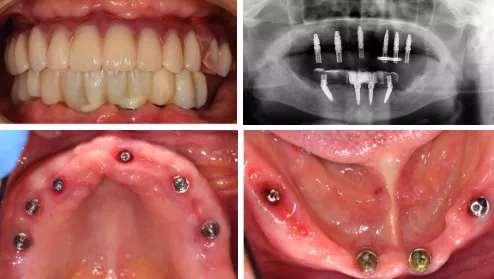

- 口腔卫生较差,21、22、27、31-33、35-37、41-45、47缺失,14金属烤瓷冠修复,16𬌗面汞充填,余牙松动Ⅲ,PD:5-8mm,BOP(+),牙龈萎缩,红肿,上下颌位关系正常,但无稳定的颌位关系。

口内检查上下颌多牙缺失

影像学检查

- CBCT示:21、22、27、31-33、35-37、41-45、47缺失,余牙牙槽骨吸收至根尖1/3。牙周膜间隙增宽。剩余牙槽骨丰满度一般。

CBCT检查见上下颌骨量